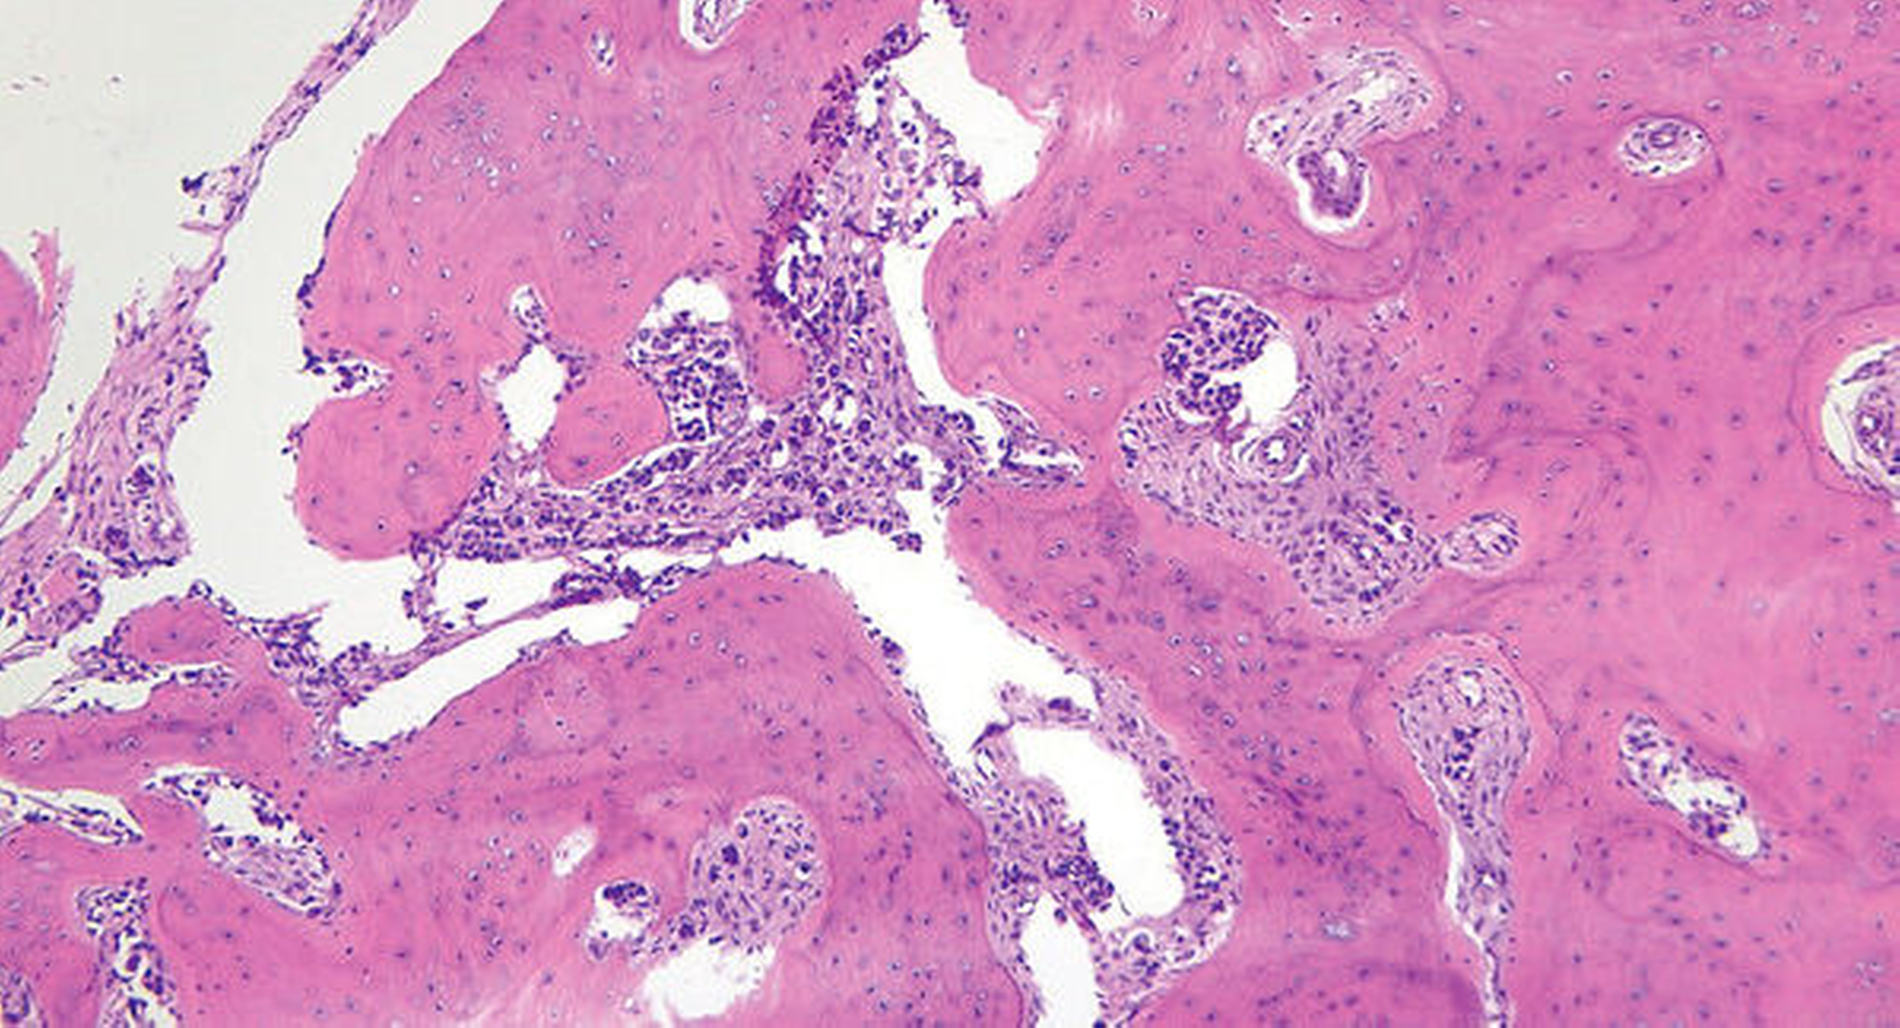

Der histopathologische Befund ergab intrakortikale Infiltrate eines stark alterierten Karzinoms mit ausgeprägter umgebender Fibrose, passend zu einer Metastase des bekannten Mamma-Karzinoms (Abbildung 3). In der immunhistochemischen Nachuntersuchung zeigten die Tumorzellen eine starke Positivität für Panzytokin, was die Diagnose einer Metastase des Mamma-Karzinoms bestätigte. Die zuvor angenommene Verdachtsdiagnose eines Zementoblastoms wurde durch die histopathologische Begutachtung also eindeutig widerlegt.